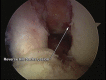

Posterior shoulder dislocation is an unusual injury often associated with electrical shock or seizure. As with anterior instability, patients frequently present with an impaction injury to the anterior aspect of the humeral head known as a "reverse Hill-Sachs lesion." The treatment of this bony defect is controversial, and multiple surgical procedures to fill the defect in an effort to decrease recurrence have been described. Most of the reports have focused on an open approach using variations of lesser tuberosity and subscapularis transfers, bone allograft, and even arthroplasty to assist with persistent instability. We advocate an arthroscopic technique that involves a suture anchor-based distal tenodesis of the subscapularis tendon or a reverse remplissage procedure.